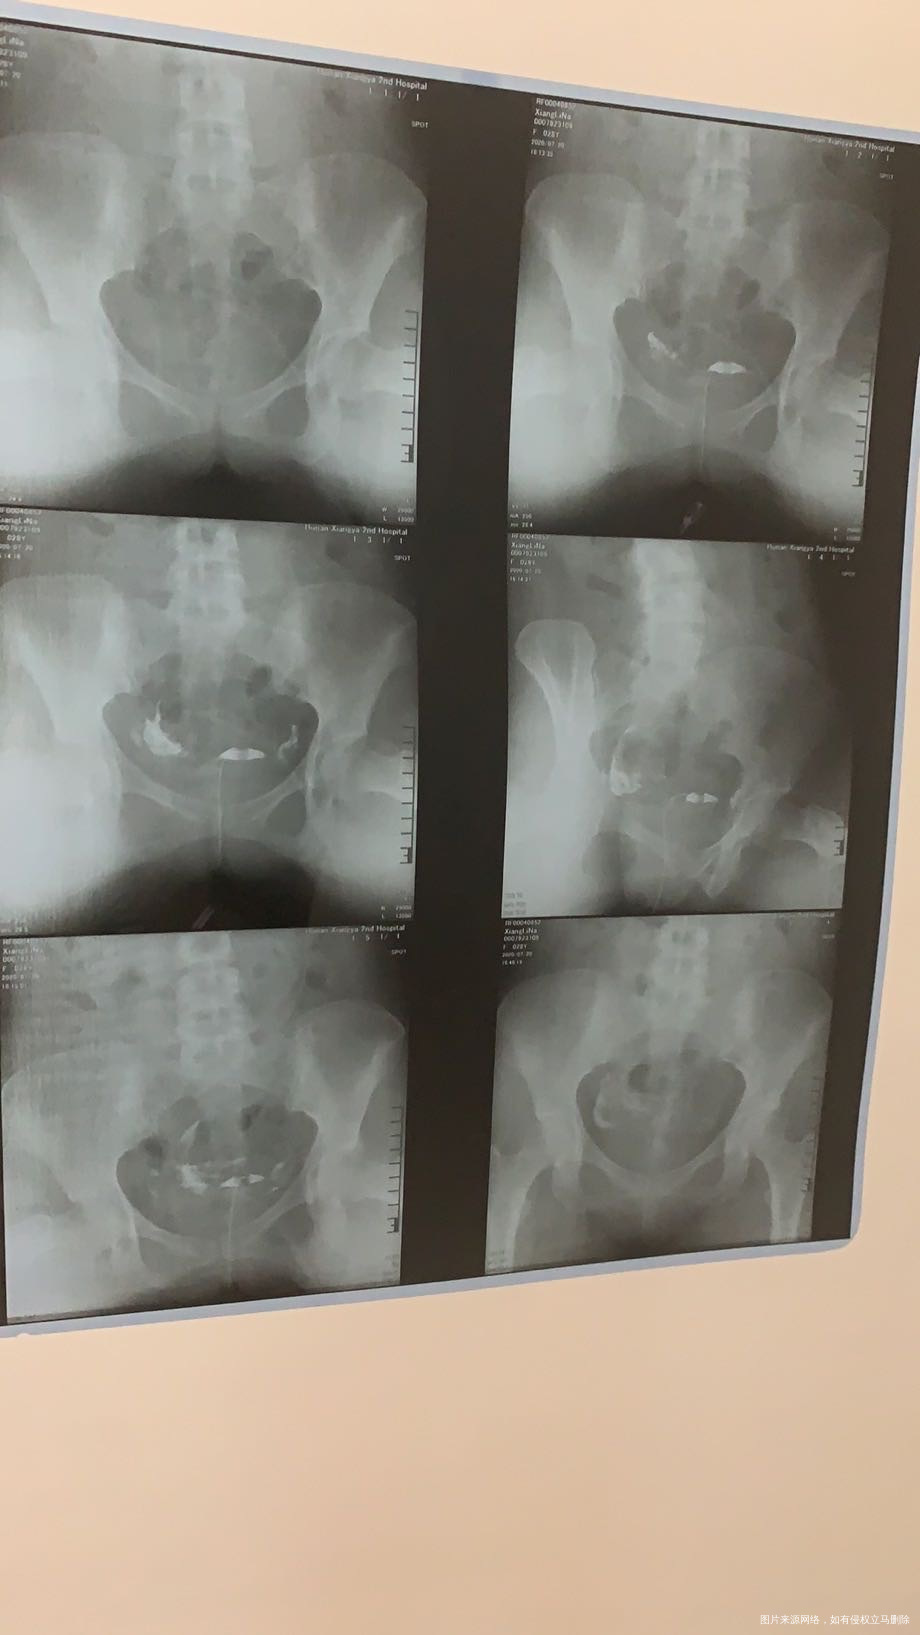

1楼一般多囊的人不会早衰,我不知道你从哪里得出的结论说是卵巢早衰,你需要完善月经期的女性激素6项,输卵管的左侧不通,右侧有粘连,可以试试输卵管通液后促排卵,尝试6月后无果可以考虑试管了

of 回复 徐敏倩:输卵管只说慢性炎症,我上个月头胎就刚刚生化妊娠了,b超这个是不是多囊?雌激素低会不会卵巢功能减退,我同房干涩很多年了,内裤也干干净净的没有分泌物

徐敏倩 回复 of:查个amh就知道卵巢功能好不好了,如果平时同房干涩的话可以用普罗雌烯阴道软膏,里面含有雌激素同房的话会好一些,卵泡多也不代表促排卵,有些人只是多囊样改变,但是也会排卵。建议你去医院系统查一下。